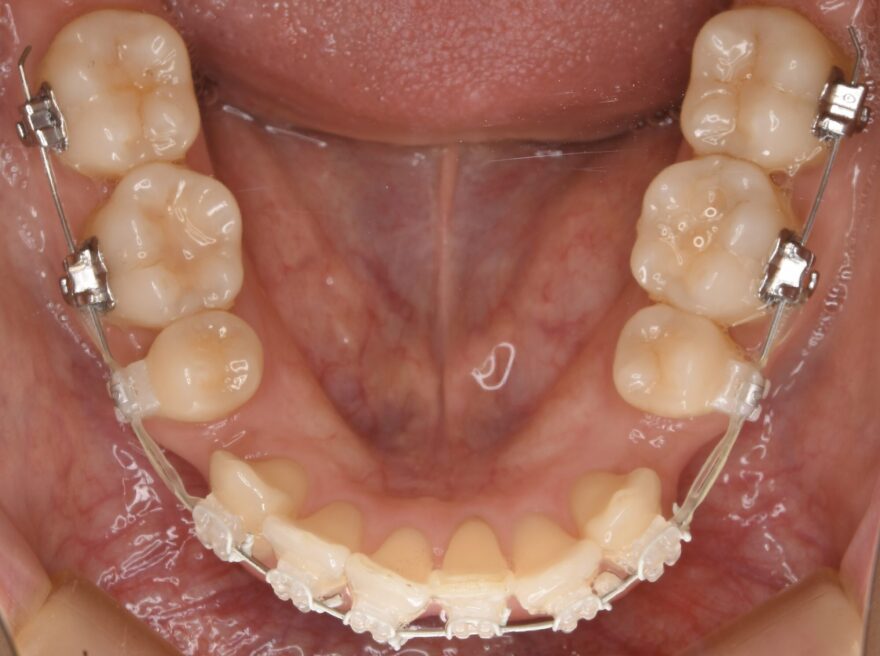

治療中の口腔内写真

上下ともには表側に矯正装置が付いています。

金属ワイヤーの外側にのみ白いコーティングがされていることが分かります。